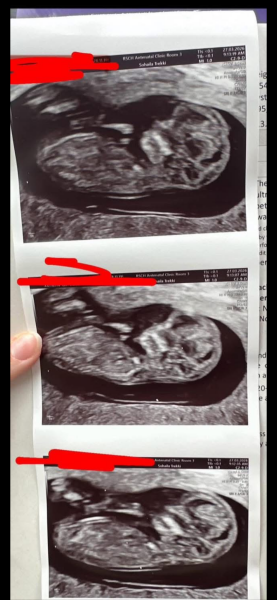

Any guesses on what baby may be!? Due Oct but these scans are a few weeks ago at our 12 week scan.

Any guesses on baby's sex from our 12 week scan? 🩷🩵💛